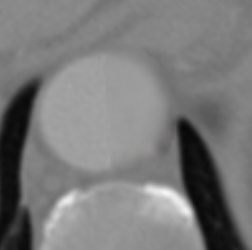

Figure 9 shows axial CTA images of an aortic dissection case. In both rows of this figure an example for executing an inpainting with the inpainting tool is given. The image section of all sub-figures is equal to the defined region of interest. The sub-figures in Figure 9 show from left to right: unedited CTA scan showing the aorta and surroundings, the mask used for the inpainting and the inpainting result. The Sub-images (a) and (b) include a dissected aorta, whereas the dissection is removed in the sub-images (d) and (f).

(c) Inpainting result

Figure 9: Two examples for an inpainting of an aortic dissection utilizing the inpainting tool.

Looking at the results presented in Figure 9, one can see that the depicted dissected aorta is successfully changed to a healthy looking aorta. But it is also noticeable, that the region reconstructed by the inpainting is slightly blurred, which could be addressed by refinement of the EdgeConnect model. The timing analysis in section 6 shows that a call of the inpainting tool is completing in around four seconds, wherein the majority is caused by executing the neural network. This indicates the code of the inpainting tool itself offers little room for speeding up the application.